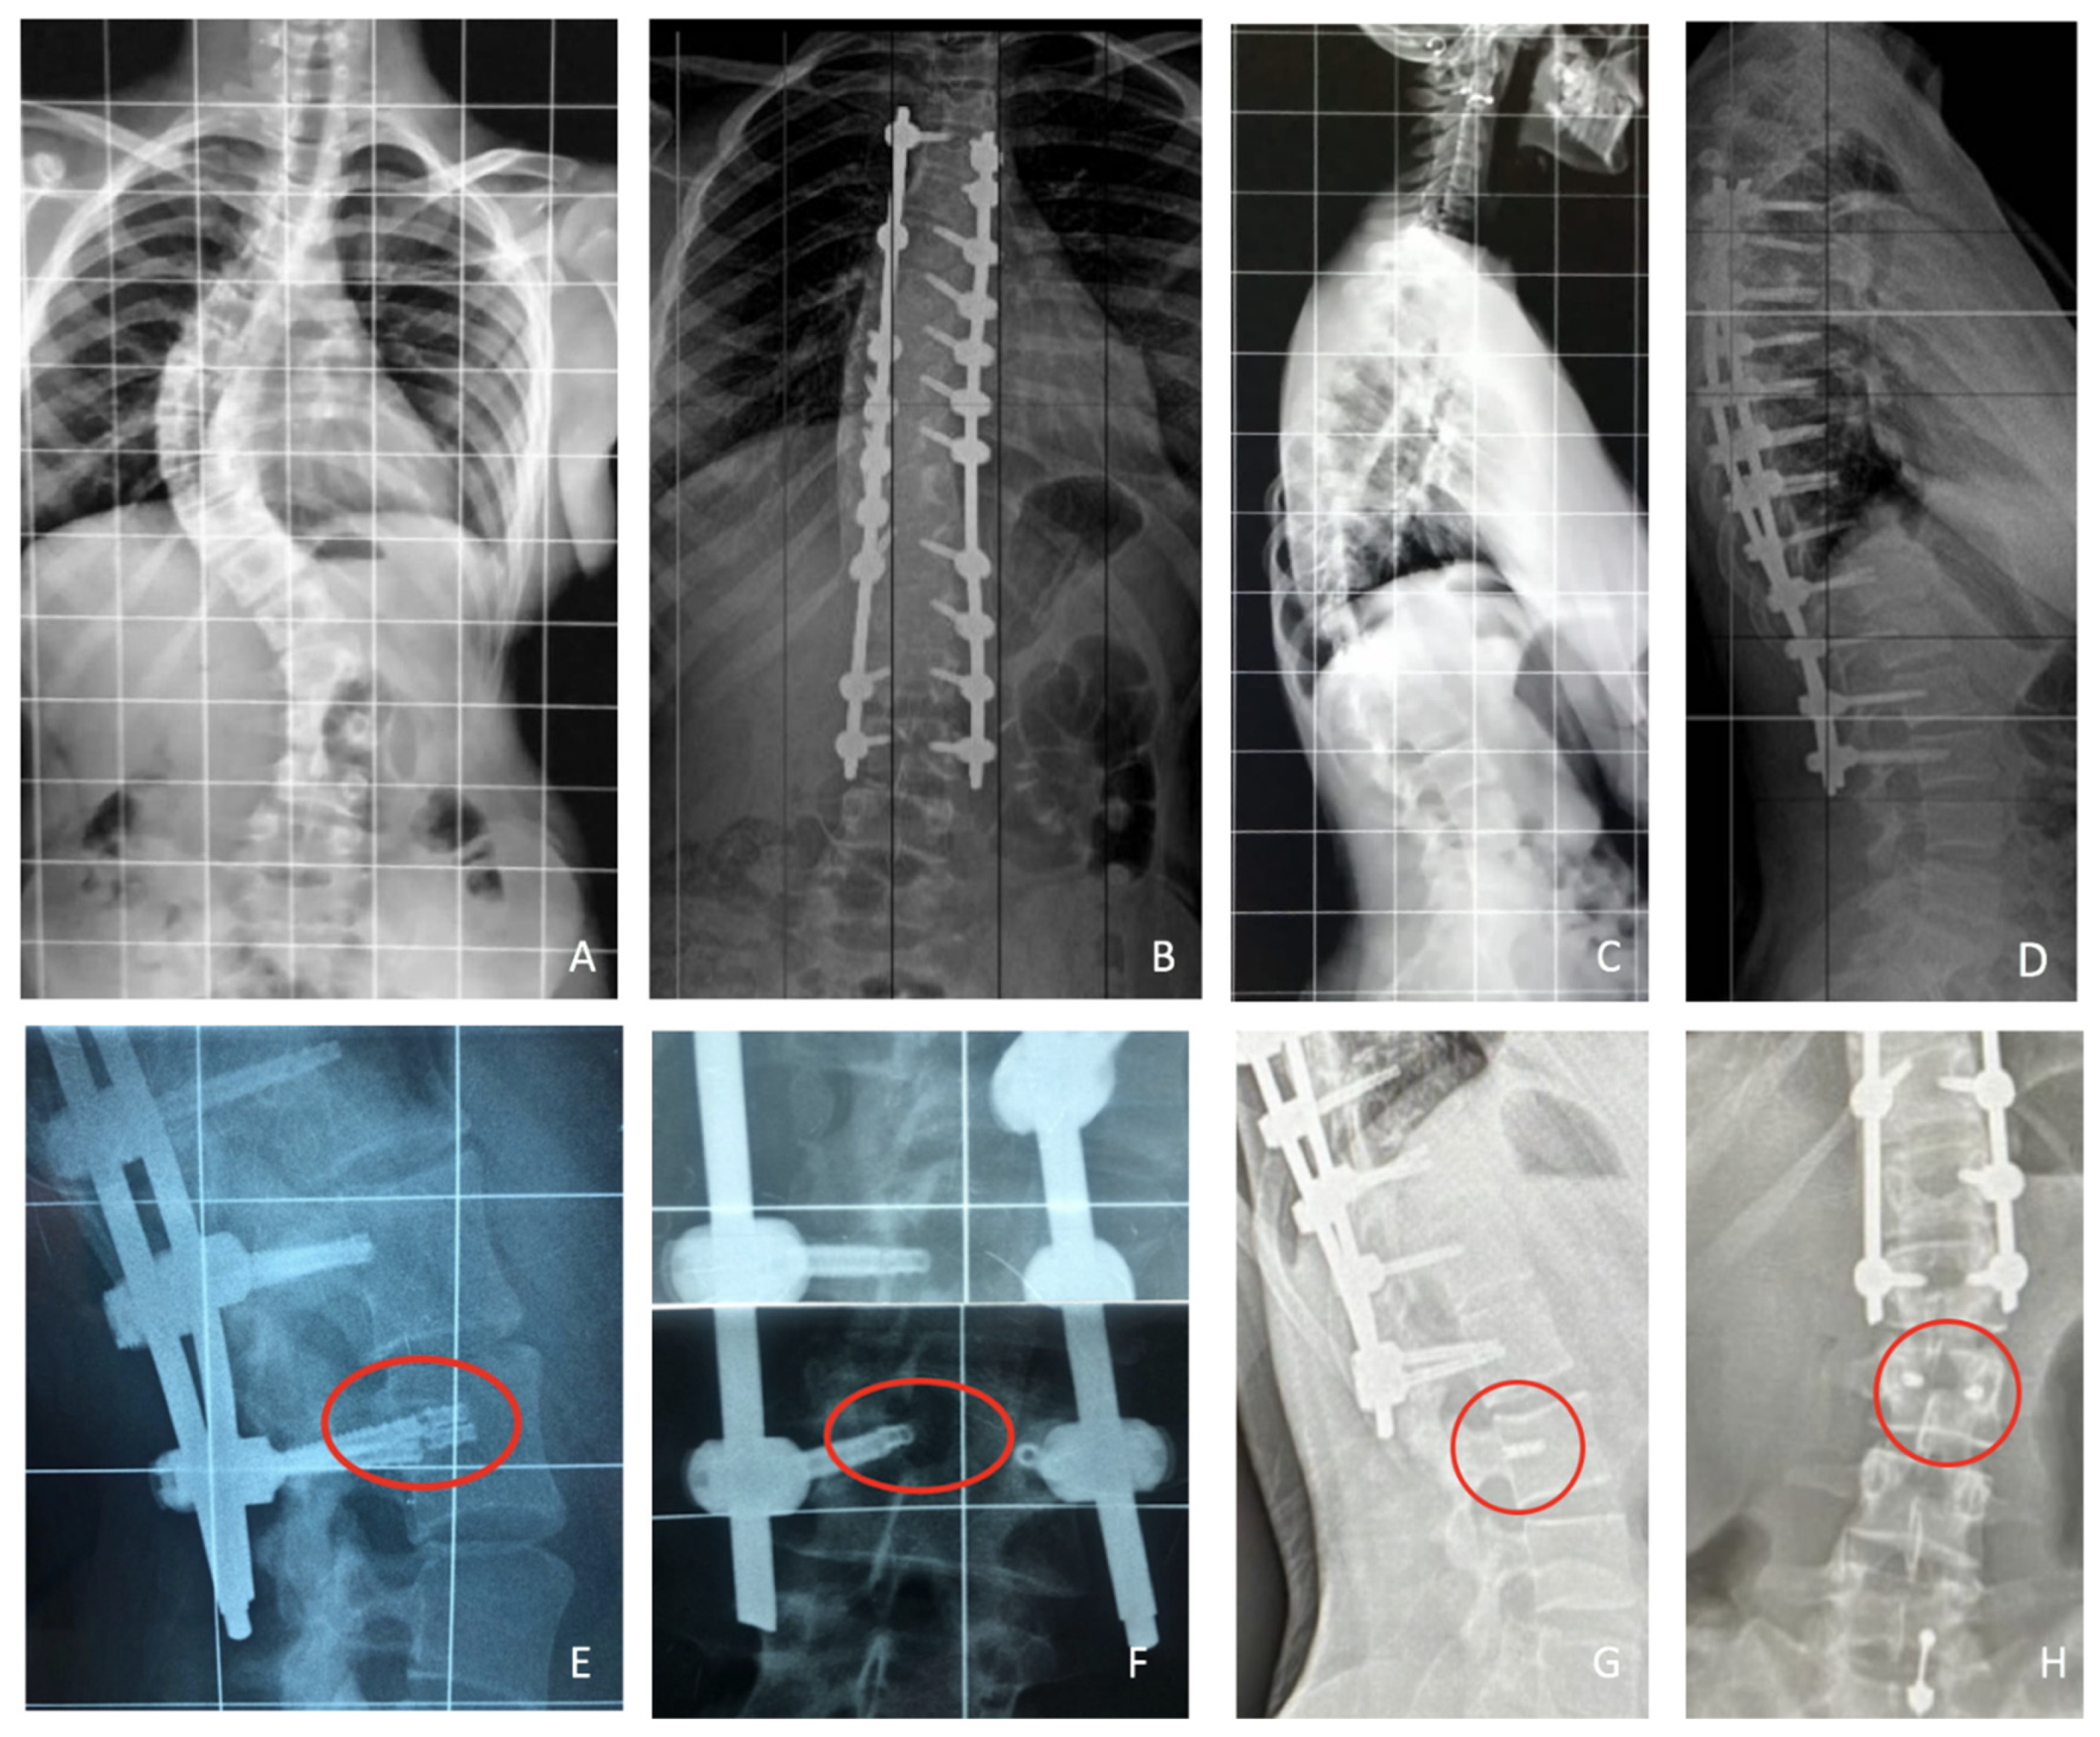

3.4. Complications